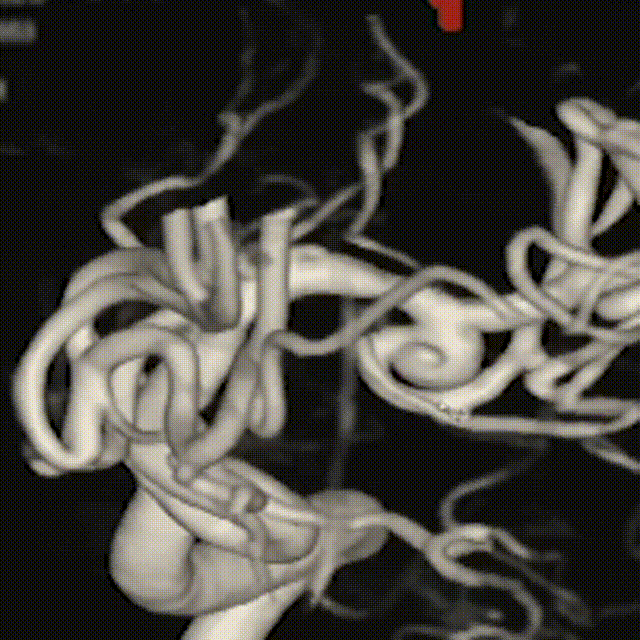

此为左侧大脑中动脉瘤,近端血管极为迂曲,瘤体有突出的子囊,动脉瘤与载瘤动脉有一定夹角,动脉瘤呈上窄下宽形状,M2段下干从瘤颈近端发出。

动脉瘤平均宽度5.41mm, 最小高度为3.71mm,瘤颈约为4.94mm,使用WEB™ SL 6*3mm瘤内扰流装置进行栓塞治疗。

释放WEB™:缓慢推出WEB™从种子至萌芽状态,继续向瘤腔内远端缓慢推送WEB™至萌芽至开花间状态;将WEB™和VIA™送至瘤顶,固定WEB™推送杆回撤VIA™,WEB™完全释放。

经造影可见WEB™尺寸合适,贴合瘤壁,覆盖瘤颈,且下支M2段分支及其他分支血管血流通畅。

解脱后,再次造影和Dyna-CT评估,可见动脉瘤瘤腔内有明显造影剂滞留,分支血管血流正常。